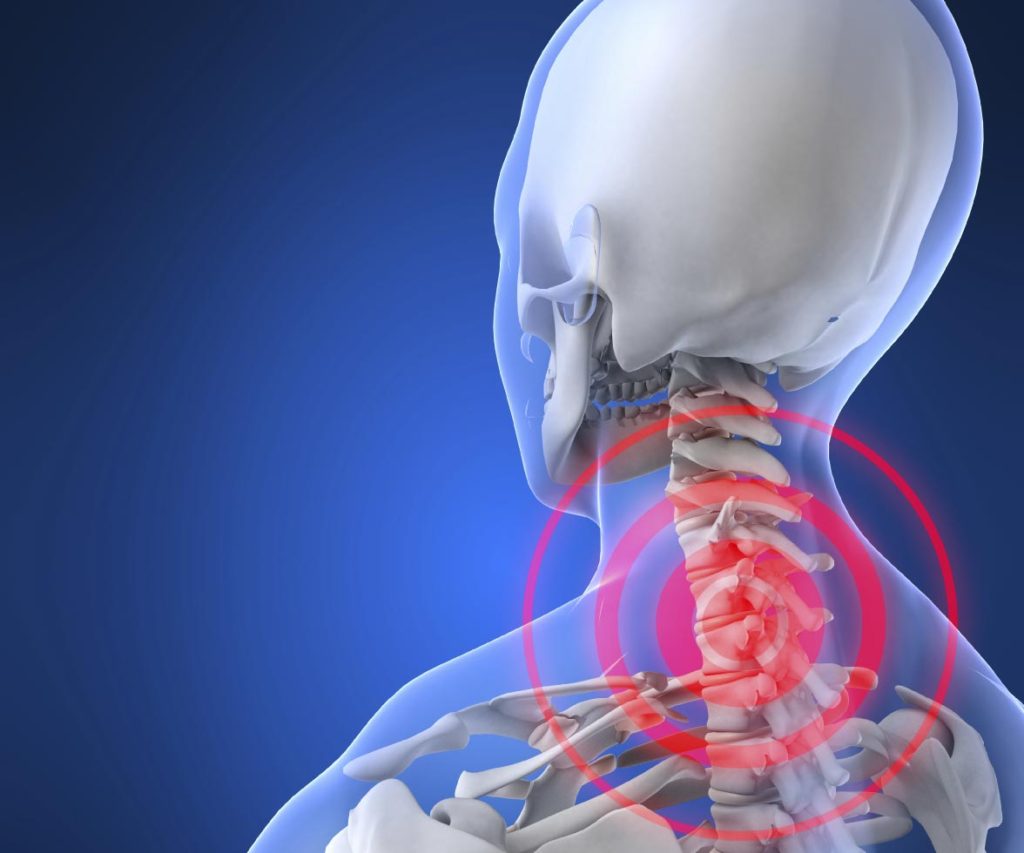

يتكون العمود الفقري العنقي من 7 عظام تسمى الفقرات، والتي يتم فصلها عن طريق أقراص مغطاه بسائل يشبه الهلام، وتسمح هذه الأقراص باستقرار الرقبة، والمزيد من السلاسة في الحركة من جانب إلى آخر، أو من الخلف للأمام.

ويتجاوز ديسك الرقبة والتنميل مجرد الألم، بالإضافة إلى وجود خدر وضعف في الكتفين و ألم الكتف والذراعين واليد، وهذه المشكلات في الحركة والتنقل تؤثر بشكل كبير على الأنشطة اليومية المختلفة في الحياة.

يقول الطبيب “كي كيم”، الأستاذ المشارك في جراحة الأعصاب ورئيس جراحة المخ والأعصاب في العمود الفقري بجامعة كاليفورنيا: إنه “بدون أقراص فلن يتم السماح لأجسادنا بالتحرك بالطريقة التي نريدها)، فهي تعمل كوسادة للجسم، تقوم بامتصاص الصدمات والتخلص تدريجيًا من أسباب الانزلاق الغضروفي.

وهناك عددًا من الأعراض الأكثر شيوعاً لديسك الرقبة، ومنها ما يلي:

عندما يحدث انفجار أو ينكسر القرص، سيضغط ذلك على الحبل الشوكي وجذور الأعصاب، والذي يعرف بـ”فتق القرص” أو انزلاق القرص، وعلى الرغم من أن مرض ديسك الرقبة يعتبر مرض بطئ التطور، لكن فتق الرقبة يمكن أن يحدث بسرعة بعد الإصابة أو الصدمة في الرقبة.